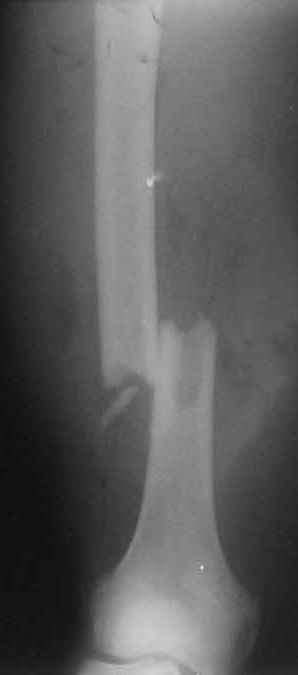

В нашем случае 21 летний боец уличного фронта, фиксацию провели на следующий день, зафиксирован интрамедуллярным штифтом. Не стали делать первичную хирургическую обработку точечной раны, зафиксирован как есть. Клинические снимки:

Конечно, наш случай не эталон, возможно, на месте вам виднее, может быть, нет необходимости ориентироваться на зарубежные ссылки, если получается лечить аппаратом Илизарова на месте, почему нет? Необходимо посмотреть собственный арсенал, чем фиксировать, и какая теория, иначе любой отличный метод можно превратить в источник остеомиелита.